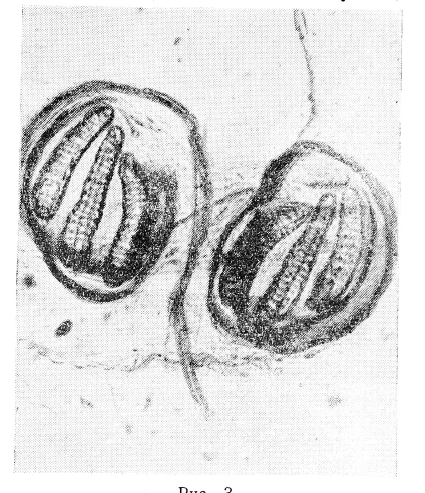

Длина этих личинок достигает 15мм, на поверхности, их имеется множество желтовато-коричневых шипиков, на заднем конце пара дыхальцевых пластинок с тремя щелями каждая (рис. 3), личинки вооружены парой больших ротовых крючков (В. Н. Беклемишев, 1949).

Рис.3

Дыхальцевые пластинки личинки третьего возраста. Оригинал (увеличено в 280 раз).